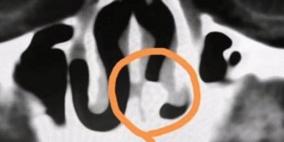

عاش 20 عاما بانسداد في الأنف.. واكتشف الطبيب المفاجأة